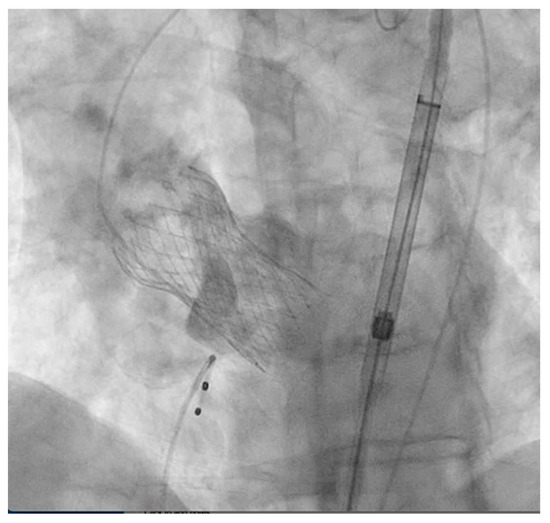

2. Detailed Case Description

3.4. Type A Aortic Dissection